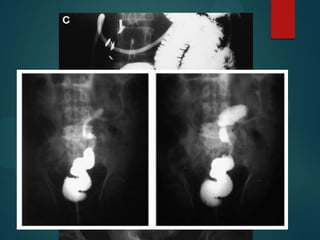

Enteroclisis y enema

   Es el “gold estándar” para detectar la existencia

OI de bajo grado y predecir el sitio y causa de

obstrucción.

   Diferenciación de ileo y obstrucción.

   Enteroclisis y TC como estudios complementarios

aumentan la precisión diagnóstica del 81 al 93 %.

   Contraindicados en sospecha de

estrangulación, perforación.

   Se realizará con sulfato de Bario.

   Revela la naturaleza de la lesión obstructiva

Enteroclisis y enema  Es el “gold estándar” para detectar la existencia OI de bajo grado y predecir el sitio y causa de obstrucción.  Diferenciación de ileo y obstrucción.  Enteroclisis y TC como estudios complementarios aumentan la precisión diagnóstica del 81 al 93 %.  Contraindicados en sospecha de estrangulación, perforación.  Se realizará con sulfato de Bario.  Revela la naturaleza de la lesión obstructiva

• #18 Enteroclisis hacer lo siguiente (B) muestra una obstrucción por adherencias banda moderadamente apretada (flecha abierta) la participación de un bucle de la pelvis de íleon. Nota retenido líquido en preestenótica dilatada (o centinela) de bucle.